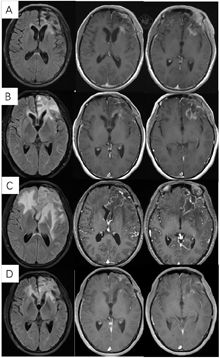

患者20年前患者体检时发现颅内占位性病变,行伽玛刀治疗,间断复查,病情稳定(图1)。20天前患者无明显诱因出现抽搐一次,伴意识丧失,持续约15分钟后逐渐恢复,至我院门诊行MR示"左侧额叶占位性病变",门诊以"颅内占位性病变"收治入院。

2018年3月、6月MR复查发现病灶范围逐渐增大(图6),提示不除外复发可能。患者除了轻微头痛之外并无明显不适,临床考虑假性进展,予安维汀100mg治疗后症状好转。2018年8月复查11C-MET PET/MR显像未见明显代谢增高病灶,证实为假性进展(图7)。2018年11月复查未见明显肿瘤复发,2019年3月2日MRI复查(图8)再次提示病变增大,考虑肿瘤进展。2019年3月行PD-1单抗(拓益)治疗,治疗过程中患者出现行走不稳,1月后患者不慎跌倒,外院就诊行颅脑CT未见明显出血。期间发现患者肝功能异常,给予护肝治疗后好转。2019年5月复查PET/MR(图9)提示左侧额叶前下部、左侧海马区及左侧颞叶前部蛋氨酸代谢较前次增高,其中左侧海马及左额叶直回ASL灌注相对增高,考虑复发可能,免疫治疗后存活。遂停用免疫治疗,根据患者全基因组测序结果选择靶向药物安罗替尼治疗(主要针对VEGFR、PDGFR、FGFR、c-KIT多个靶点),2019年12月复查PET/MR(图10)提示病变活性受抑。电话随访得知患者因武汉疫情影响无法按期治疗和复查,后合并肺部感染,于2020年8月去世。